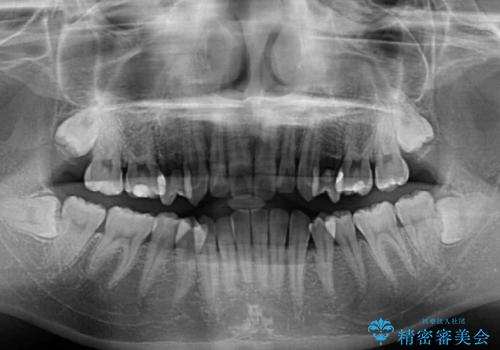

- 奥歯の反対咬合を気にして来院された患者様です。

反対咬合は上顎骨の幅が下顎骨よりも小さいことが原因なので、拡大装置により骨幅を広げて上下関係を改善し、その後インビザラインにて歯並びを整えることとしました。

反対咬合が改善され、食いしばり癖もなくなり、顎関節の負担が軽減されました。

上顎骨を拡大したことで前歯に隙間ができ、1ヶ月ほど恥ずかしい時期がありましたが、しっかりとした咬み合わせに仕上がり、患者様には大変満足していただきました。